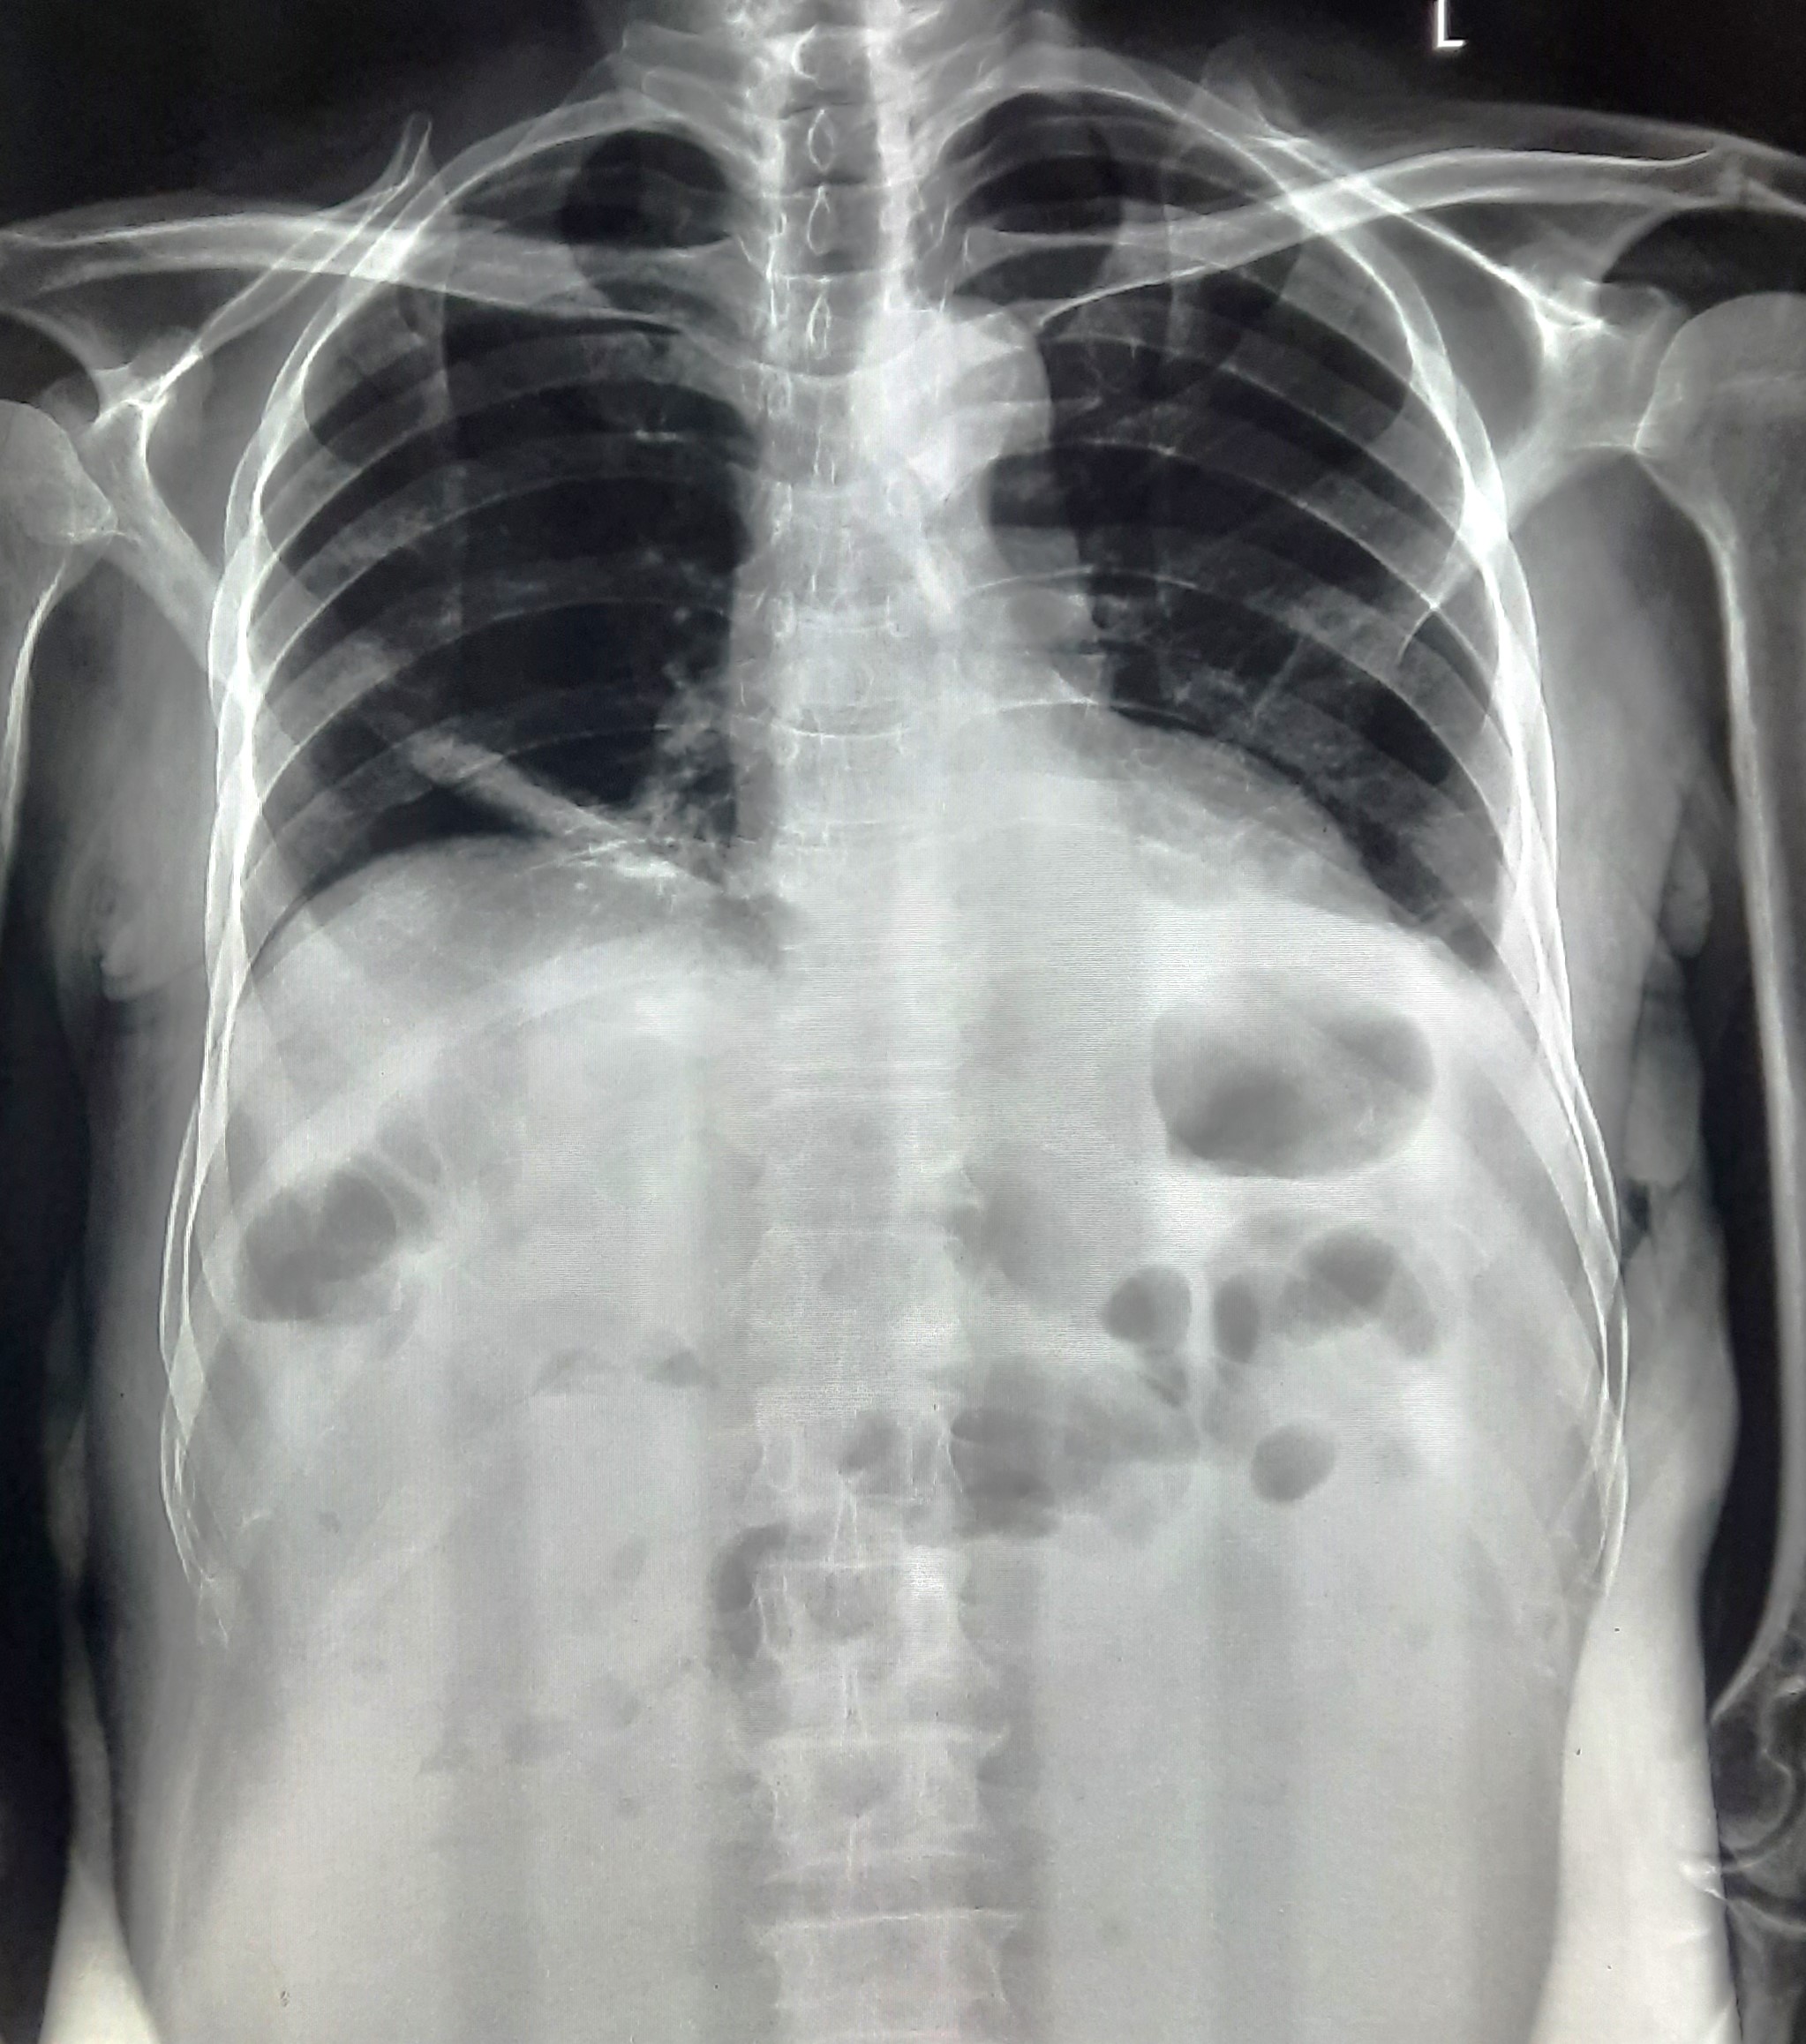

| 53 | IGGMC, Nagpur, Nagpur | P2 | 29-4419 | Rasul Ali | Consent taken on Paper | 36 Yrs. |

Provisional Diag : ?

Final Diag : COPD |

Non-TB Case (Confirmed) | Prominence of broncho vascular markings in bilateral Mid zone il Defined Non-Homogenous Lesion, Changes Of COPD | Abnormality visible on x-ray |